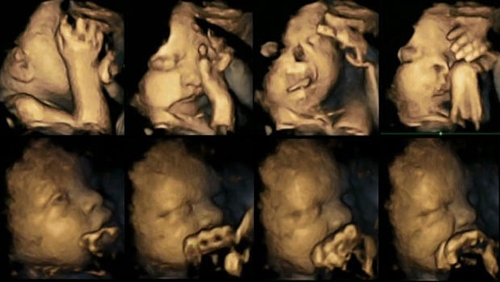

Hình chụp siêu âm 4D cung cấp thêm các bằng chứng cho thấy tác hại của việc hút thuốc lá đối với em bé...